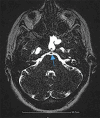

Cerebrospinal fluid (CSF) rhinorrhea is a relatively rare medical condition characterized by the drainage of CSF through the nasal cavity. Cerebrospinal fluid leakage can be attributed to a plethora of different causes, mostly traumatic or iatrogenic, but it can also be spontaneous. Due to its rare entity, CSF rhinorrhea is often a diagnostic trap and can be misdiagnosed and mistreated as rhinosinusitis or allergic rhinitis. This can result in severe complications, such as meningitis, which could potentially have life-threatening consequences if not accurately identified and managed. In this case report, a 53-year-old Caucasian woman presented at the emergency department with symptoms of headache, fever, transparent nasal discharge from her left nostril when leaning forward and mild neck stiffness. Based on the patient's clinical presentation and physical examination findings, there was a high suspicion of central nervous system infection and cerebrospinal fluid leakage. A lumbar puncture confirmed the diagnosis of meningitis, while imaging exams, including computed tomography (CT) and magnetic resonance imaging (MRI) scans, revealed a fistula between the posterior wall of sphenoid sinus and the subarachnoid space. Additional findings included an empty sella turcica, suggesting a potential underlying cause for this condition and an incidental meningioma near the area of leakage. The patient received empiric intravenous antibiotic therapy and was discharged after ten days. She was referred to the neurosurgical department for surgical repair of the CSF leak and removal of the meningioma, in line with appropriate treatment guidelines. This study highlights the importance of promptly identifying and thoroughly investigating potential causes of CSF leakage to provide appropriate medical management.